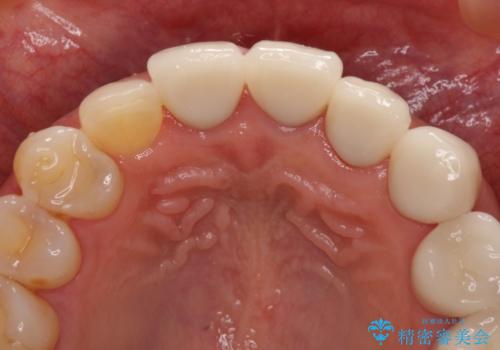

- 前歯の歯肉の高さが左右で異なっていることを気にして来院された患者様です。

歯肉レベルを調整するために歯周外科処置をおこない、その後にオールセラミッククラウンにて補綴することとしました。

処置後の痛みはあまり気にならず、歯肉位置の左右差もほとんどなくなり、患者様には大変満足していただきました。